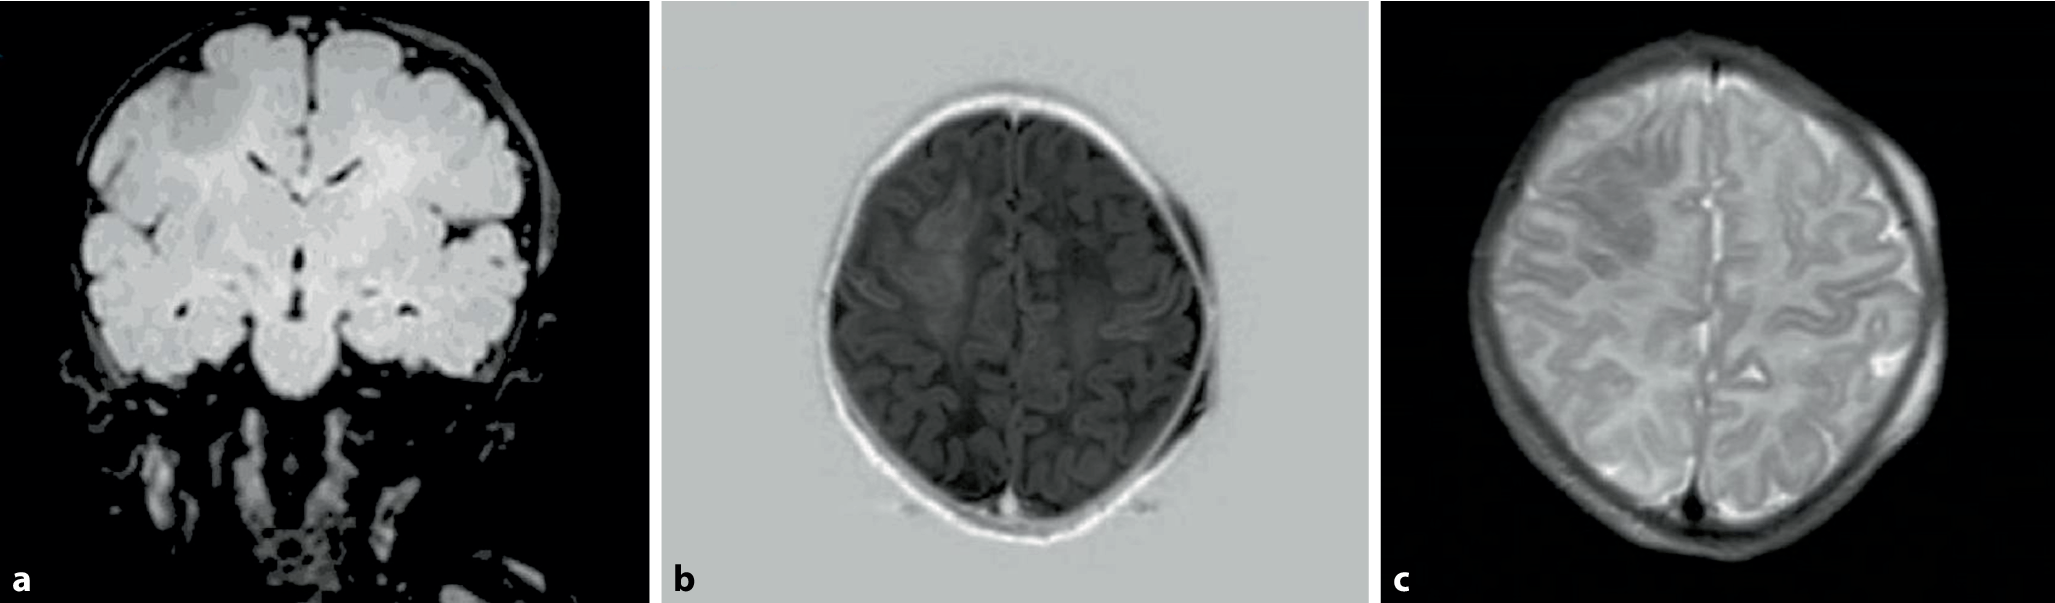

Am Vortag fiel erstmals auf, dass das sechs Tage alte Neugeborene wiederholt für einige Sekunden mit dem linken Arm zuckte. Am folgenden Tag drehte es im wachen Zustand mehrmals für etwa zwei Minuten den Kopf und die Augen nach links. Laut Eltern waren Schwangerschaft und Geburt unauffällig. Abb. 1, 2 und 3 zeigen die Hirnsonographie, die kranielle Magnetresonanztomographie (MRT, am neunten Lebenstag) und das Elektroenzephalogramm (EEG).

Abb. 2

Kranielle Magnetresonanztomographie (MRT) am neunten Lebenstag. Sequenzen: a FLAIR, b T1-IR, c T2-TSE